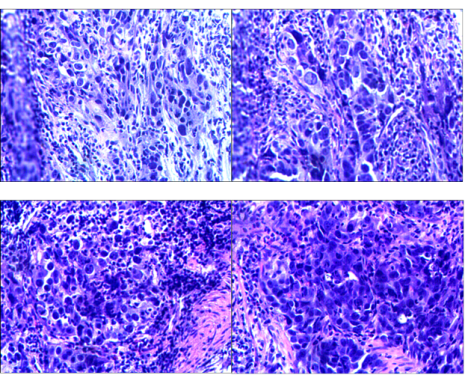

2021.02.24:外院胃镜活检组织病理切片提示胃角低分化腺癌,lauren分型:弥漫型。

图2 胃镜活检组织病理切片